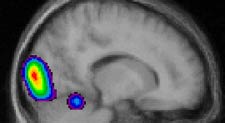

Coupe sagittale en

TEP durant la tâche d’imitation avec la main droite: l’activité

principale a lieu dans le cortex visuel et l’activité secondaire

dans le cervelet (coordination motrice).